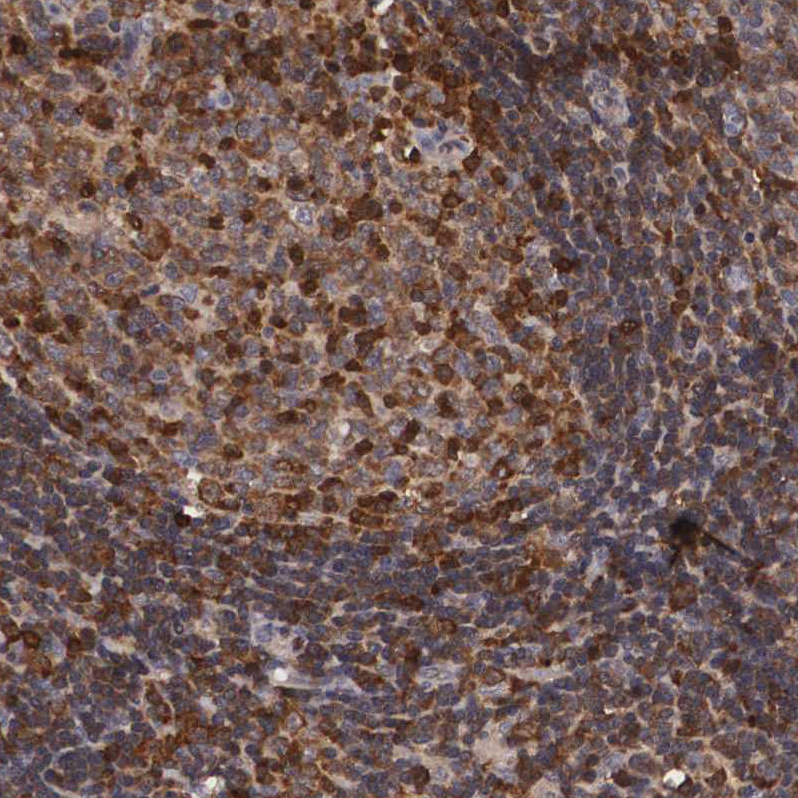

Immunohistochemical staining of human skeletal muscle shows moderate cytoplasmic positivity in myocytes.